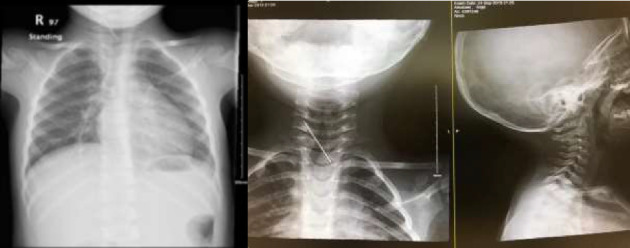

颈椎异物的病例被认为是罕见的,而针头移入椎管的病例是相当罕见的。记录最充分的案例是针灸针。我们报告一个2岁男孩的病例,偶然发现静脉注射针向后延伸至C7和T1棘间间隙,并在C5-C6间隙结束。我们讨论了可能的入境口岸和对这些发现的处理。

Cases of cervical foreign bodies are considered rare, and cases of needle that have migrated into the spinal canal are fairly uncommon. The most well-documented cases are those of acupuncture needles. We present a case of an incidental finding of an intravenous needle extending posteriorly between C7 and T1 interspinous space and ending at the level of C5-C6 interspace in a 2-year-old boy. We discuss the possible port of entry and the management of such findings.